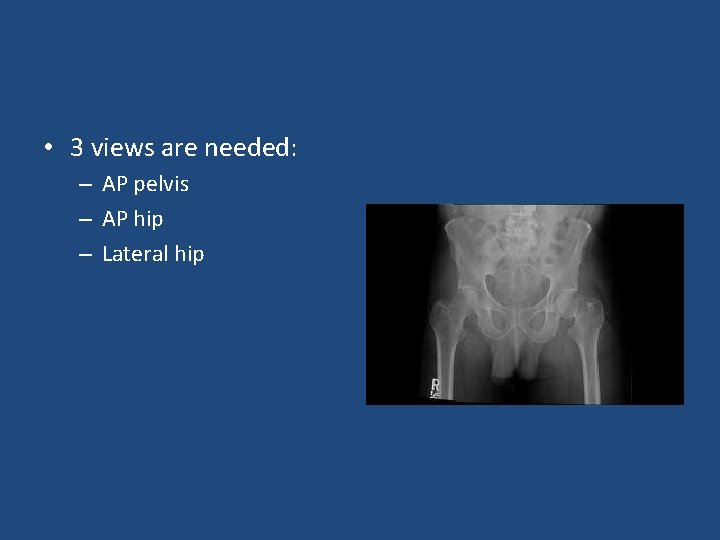

• 3 views are needed: – AP pelvis – AP hip – Lateral hip